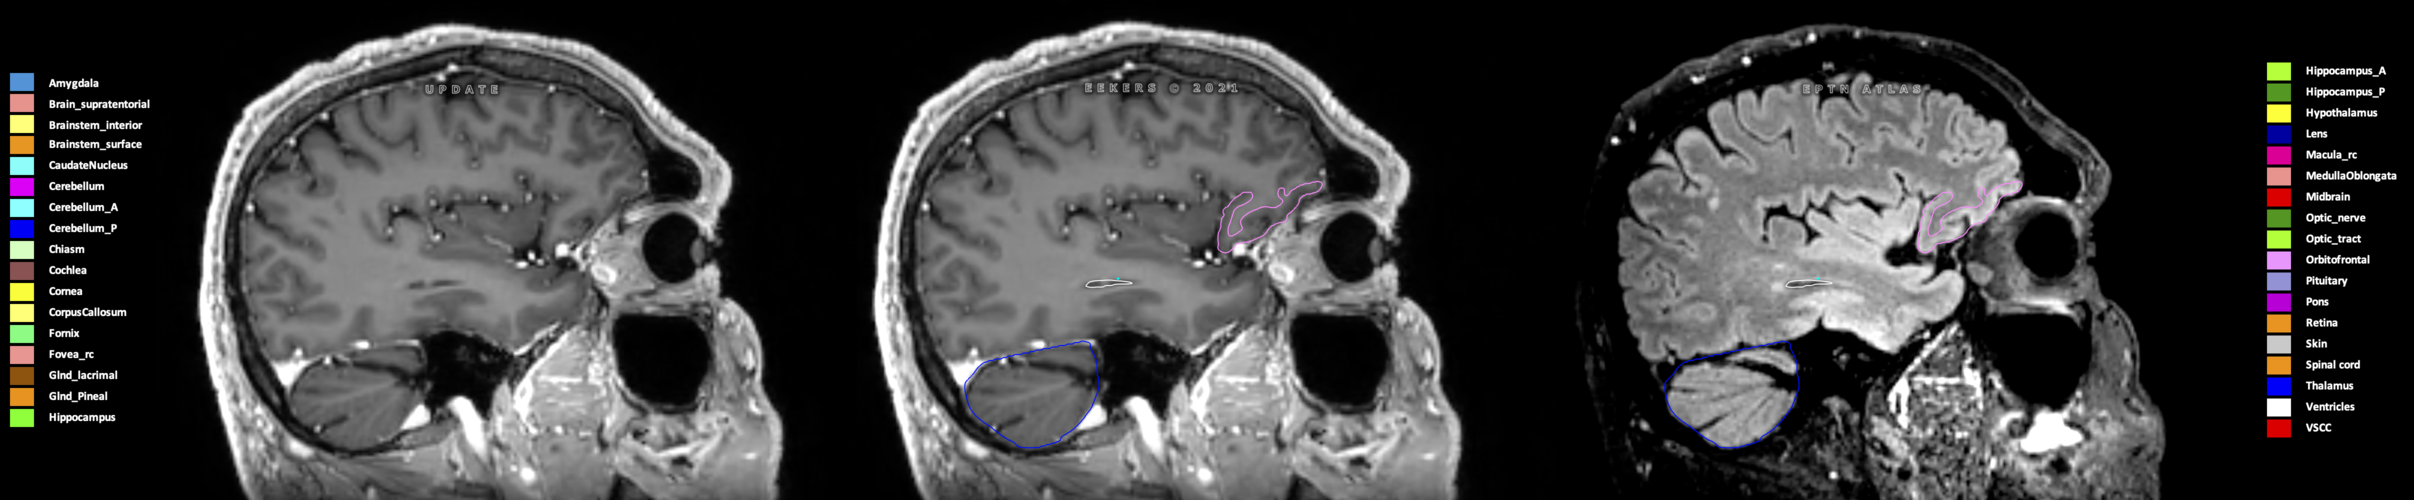

Eekers et al. have published an international neurological atlas for contouring of organs at risk in consensus with the European Particle Therapy Network (EPTN) in 2018 and an update in 2021. The purpose of this consensus atlas is to decrease inter- and intra-observer variability in delineating OARs relevant for neuro-oncology.

Included are all OARs known to be relevant for radiation-induced toxicity in neuro-oncology: brain, brainstem (midbrain, pons, medulla oblongata), chiasm, cerebellum (anterior & posterior), cochlea, cornea, hippocampus (anterior & posterior), hypothalamus, lens, lacrimal gland, optic nerve, pituitary, skin, and vestibular & semicircular canals. To further facilitate research on cognition, vision and radiological changes after irradiation of the brain, potential clinically-relevant OARs are included: amygdala, caudate nucleus, cerebellum (anterior & posterior), corpus callosum, fornix, macula, optic tract, orbitofrontal cortex, periventricular space (PVS), pineal gland, and thalamus.

Three-dimensional delineation of the 25 consensus OARs for neuro-oncology are shown on CT (WW/WL 120/40, 3000/600), 3T MR images, (T1Gd, T2FLAIR 1mm) and 7T MR (MP2RAGE 0.7 mm). All are presented in transversal, sagittal and coronal view.